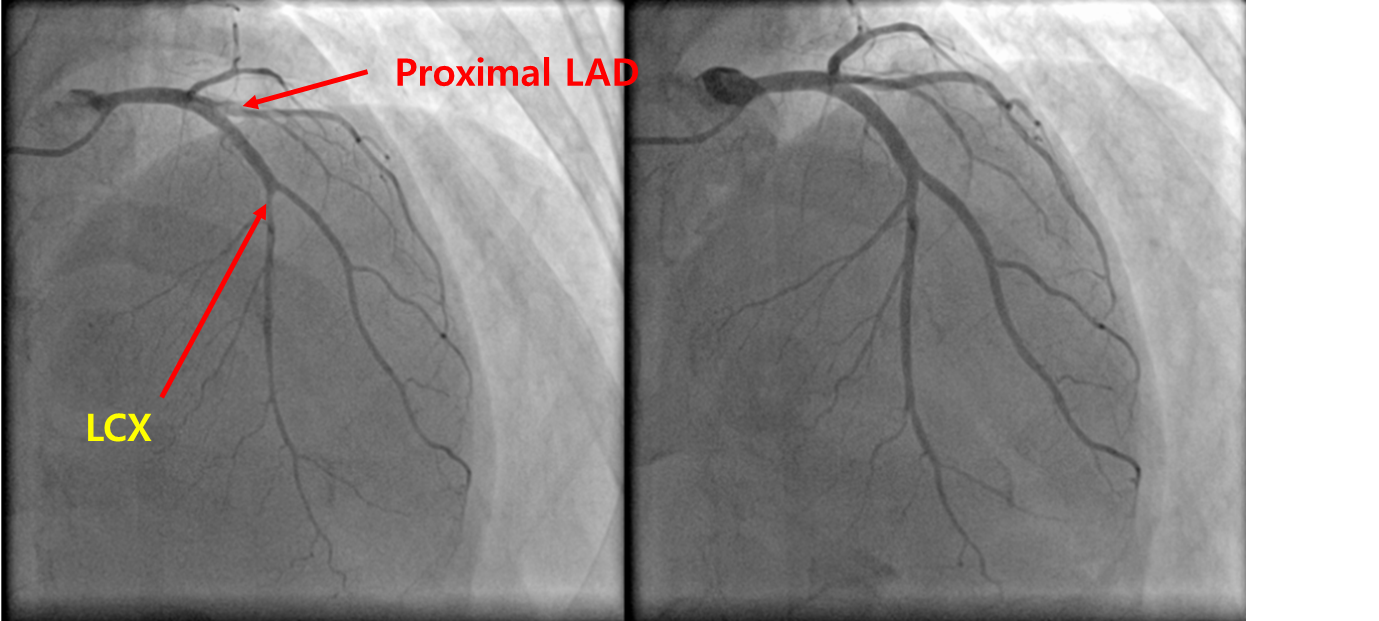

40세 남자가 3개월 전부터 가슴이 아파서 병원에 왔다. 야간 근무 후 새벽에 퇴근할 때마다 쥐어짜는 듯한 통증이 발생하였고 운동할 때는 통증이 없었다고 한다. 30갑년의 흡연자이다. 혈압 110/70 mmHg, 맥박 70회/분, 호흡 20회/분, 체온 36.5 ℃이다. 가슴 청진에서 심음과 호흡음은 정상이다. 혈액검사 결과는 다음과 같다. 심전도이다. 에르고노빈과 니트로글리세린을 각각 관상동맥에 주입한 후의 관상동맥조영술 사진이다. 진단은?

• 변이 협심증의 진단을 위해 관상동맥조영술(coronary angiography, CAG)을 시행, 관상동맥에 ergonovine을 투여할 때 전반적으로 동맥이 수축하고, 혈관확장제인 nitroglycerin을 투여할 때 다시 확장되는 소견을 보인다. 이로써 변이 협심증으로 진단한다.